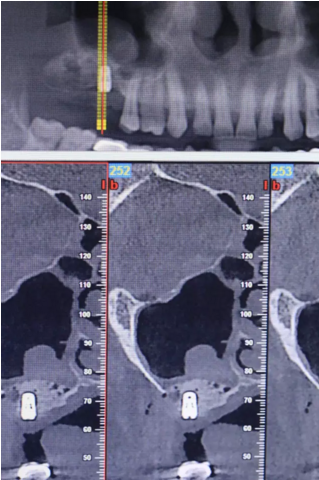

【病例分享】上頜竇大囊腫外提升